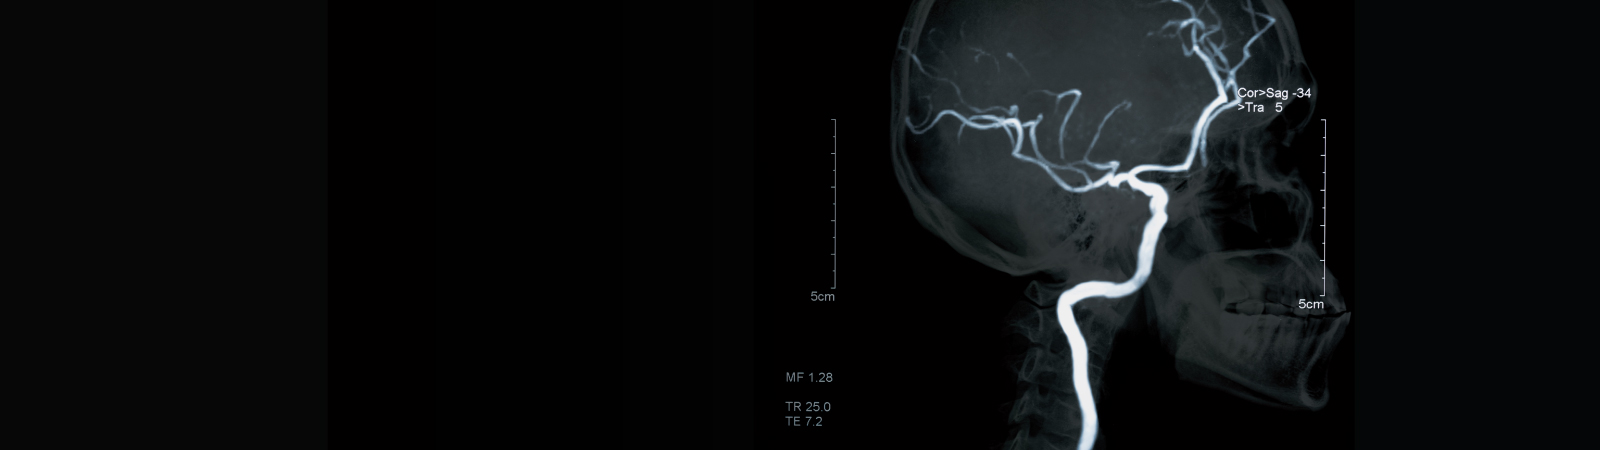

• Angiogram: An angiogram is a test that uses X-rays to check the blood vessels for damage. Dye is injected into the vessels through a catheter, allowing them to be visible on the X-rays.

• Magnetic resonance imaging (MRI): An MRI is a safe and painless test that uses radio waves and magnets to create a detailed view of the inside of the body.

• Other tests: including CT or MR angiography, or cerebrovascular reserve testing with CT or MRI.